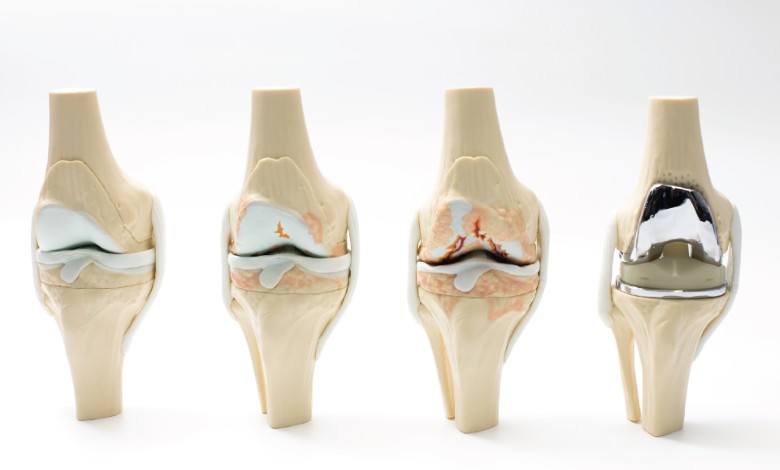

ข้อเข่าเสื่อม (Knee Osteoarthritis) เป็นความผิดปกติของข้อต่อที่เกิดจากการสึกหรอของกระดูกอ่อนผิวข้ออย่างช้า ๆ ส่งผลให้กระดูกต้นขาและกระดูกหน้าแข้งเสียดสีกันขณะเคลื่อนไหว เกิดอาการปวดที่เพิ่มขึ้นตามเวลาและอายุที่มากขึ้น ร่วมกับการเปลี่ยนแปลงภายในข้อ เช่น กระดูกอ่อนบางลง การเกิดกระดูกงอกรอบข้อ และการเปลี่ยนแปลงของน้ำหล่อเลี้ยงข้อ

ลักษณะอาการที่พบบ่อย ได้แก่ ปวดเข่าเรื้อรัง ค่อยเป็นค่อยไป ปวดมากขึ้นเมื่อเดินหรือใช้งานนาน มีอาการฝืดในช่วงเช้าหรือหลังนั่งพักเป็นเวลานาน มีเสียงกรอบแกรบขณะงอเข่า และในบางรายอาจพบข้อเข่าผิดรูปหรือโก่งงอ โดยทั่วไปอาจมีบวมเล็กน้อย แต่ไม่ใช่อาการอักเสบเฉียบพลัน

แนวทางการรักษาขึ้นอยู่กับสาเหตุและความรุนแรงของอาการ โดยข้อเข่าเสื่อมมักเริ่มจากการรักษาแบบไม่ผ่าตัด เช่น การปรับพฤติกรรม ลดน้ำหนัก การทำกายภาพบำบัด เสริมความแข็งแรงของกล้ามเนื้อรอบข้อ การใช้ยา หรือการฉีดยาเข้าในข้อเพื่อลดแรงเสียดสี